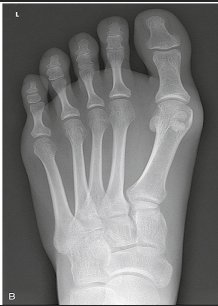

Name this projection.

Describe the position of the patient.

Where does the CR enter?

What is demonstrated?

The ________ metatarsals should be free of superimposition.

3rd-5th

Which metatarsals should be superimposed?

1st and 2nd

What could be done to demonstrate the opposite aspect of the foot?

Rotate the foot out laterally 30 degrees